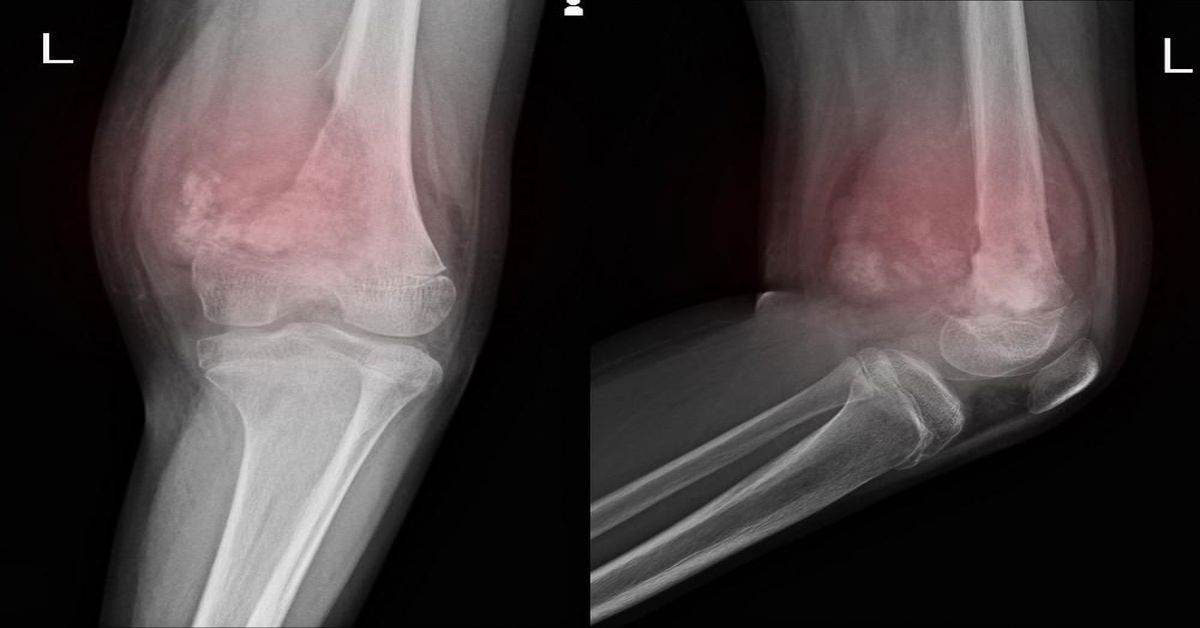

Tedavi süreci, tümörün yapısına ve konumuna göre değişir. Bu nedenle yumuşak doku tümörü tedavisi her hasta için ayrı bir planlama gerektirir. İlk adım, tümörü doğru tanımlamaktır. Muayene, MRI veya ultrason gibi görüntüleme yöntemleri ve biyopsi bu aşamada temel rol oynar. Bu incelemelerin amacı hem tümörün sınırlarını görmek hem de yapısını netleştirmektir. Böylece hangi yöntemin en etkili olacağı daha doğru belirlenir.